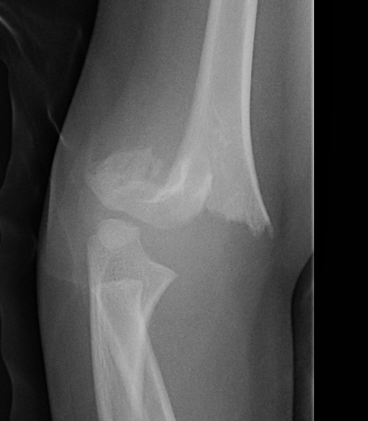

Lateral Xray

Position for good lateral

- thumb vertical

- hand above elbow

Anterior angulation

- shaft - condylar axis

- normally 40o

Lines

Anterior humeral line (AHL)

- should pass through middle of capitellum

Radio-capitellar line

- pass through capitellum

Teardrop

- shadow above the capitellum

- anterior dense line: posterior margin of the coronoid fossa

- posterior dense line: anterior margin of the olecranon fossa

- inferior portion: ossification center of the capitellum